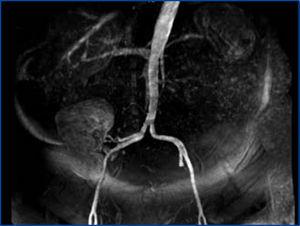

En los estudios de imagen presentaba radiografía de tórax normal y ecografía renal con riñón derecho sin alteraciones estructurales, salvo presencia de dos quistes simples en polo superior y sin poder visualizar el riñón izquierdo. Posteriormente, se realizó un angiotac de arterias renales que objetivó una estenosis casi completa de arteria renal derecha, de 1,3 cm de longitud, a una distancia de 2 cm aproximadamente de su salida, con un aneurisma de 8 mm posterior a la estenosis con presencia de alguna dilatación aneurismática más de menor tamaño. Asimismo, presentaba atrofia renal izquierda (figura 1). Este hallazgo se confirmó con una arteriografía renal.

Figura 1. Angiotac de arterias renales